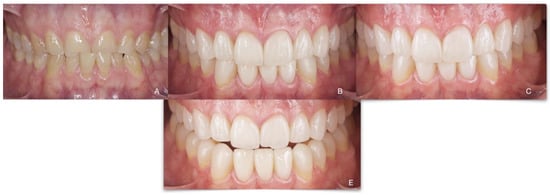

Total Rehabilitation Using Adhesive Dental Restorations in Patients with Severe Tooth Wear: A 5-Year Retrospective Case Series Study

- Final esthetics: anterosuperior vestibular veneers to achieve our final esthetic goals planned in the diagnostic process.

3. Results